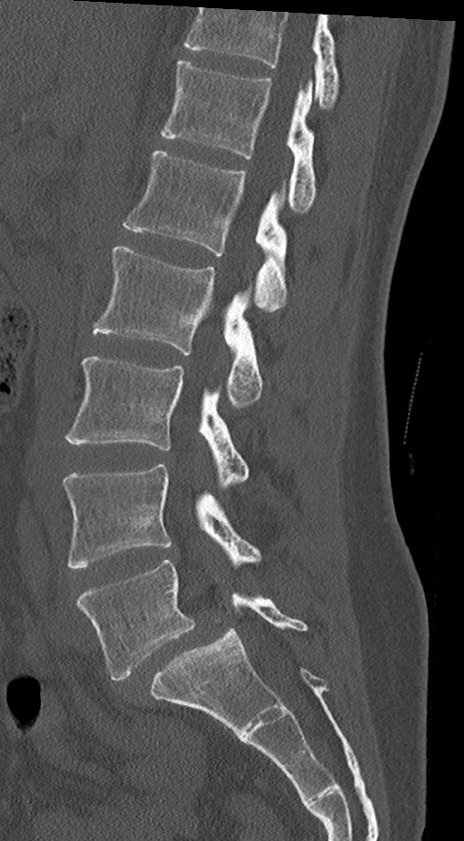

腰椎CT

横断像